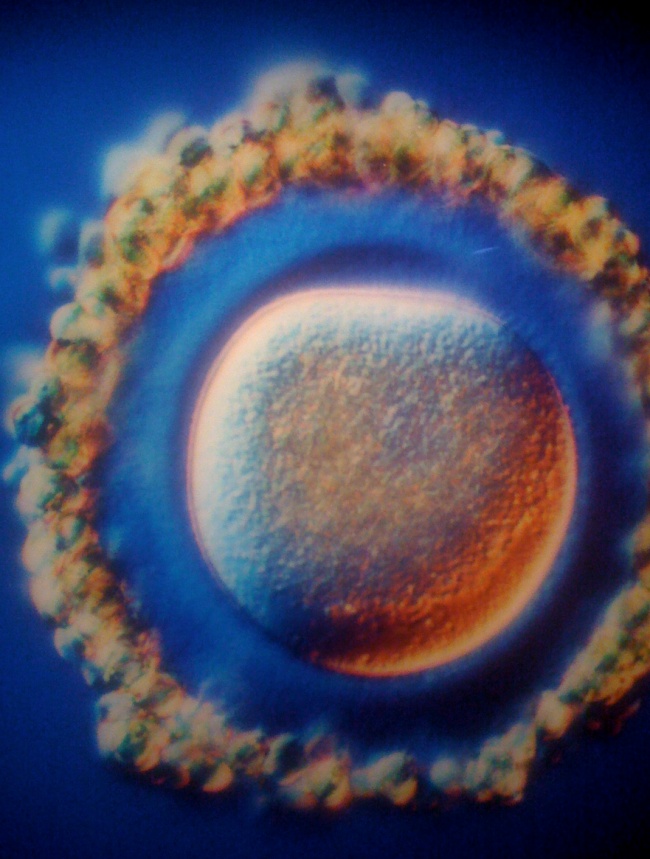

2 The egg